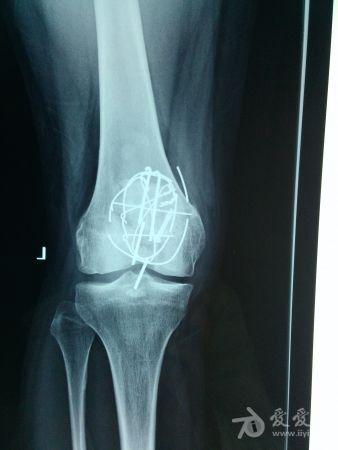

患者男性,34岁,左髌骨粉碎型骨折术后2年余。今日来诊诉局部轻微外伤后疼痛。查体:髌骨下缘钢钉有触痛,(但当时手术医生嘱咐:“无需内固定取出”……)请问各位专家同道:可以剪断髌骨下缘疼痛的钢钉吗?

髌骨内固定术后,部分内固定物断裂,不知道膝关节活动的怎么样,如果可以的话,还是建议取出全部的内固定物,但是术前一定要告知手术创伤较大,也可能部分内固定物无法取出。